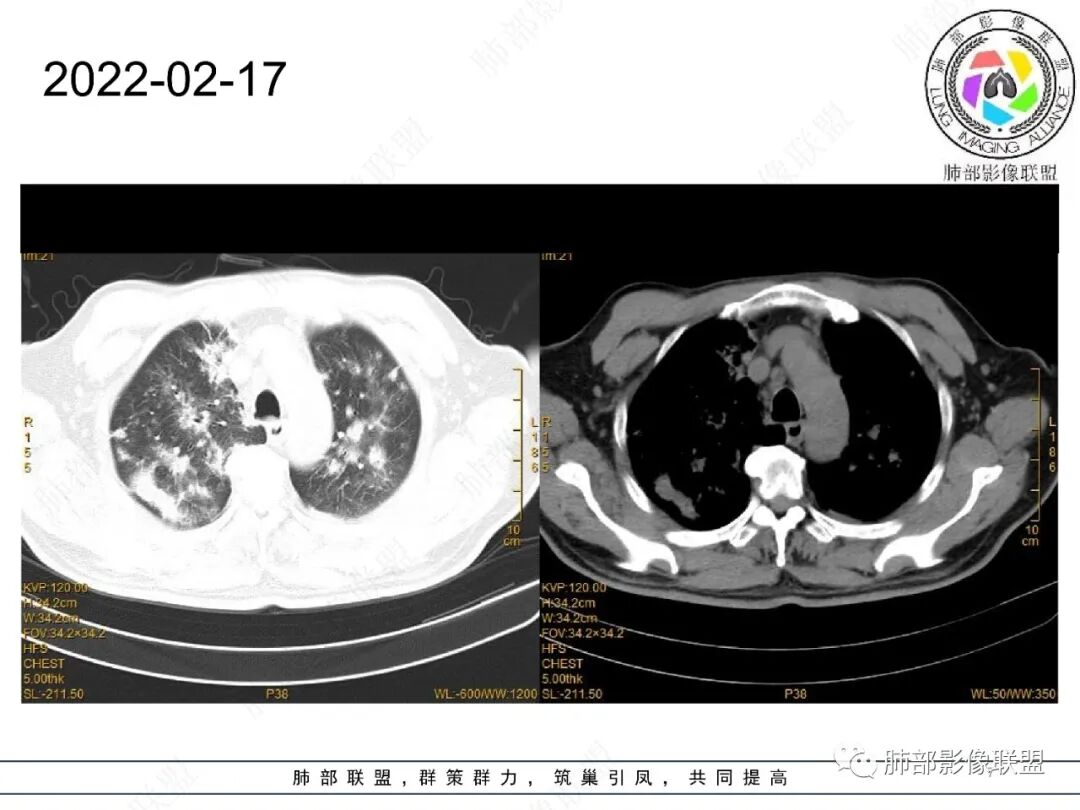

65岁男性。2022.2.17因声音嘶哑入院检查发现肺部病变,未规范治疗出院。2022.4.10因胃出血急诊入院,病情稳定后有咳嗽转入呼吸科治疗,无咳痰、无发热、无呼吸困难。白细胞、中性粒细胞轻度升高,血沉升高,抗髓过氧化物酶抗体IgG阳性,余实验室检查(-)。

2022.2.17CT显示两肺中内带多发结节影、斑片影、条索影,部分病灶侧向融合与胸膜平行。部分病灶沿着支气管血管束分布、其内支气管稍扩张。部分病灶呈反晕征。大部分病灶边界显示清晰,部分病灶周围可见边界不清的GGO。2022.4.12CT显示两肺中内带多发结节影、条索状、条带状高密度影,边界收缩平直凹陷,大部分病灶沿着支气管血管束分布,亦有位于胸膜下侧向融合与胸膜平行的病灶。总体与第一次CT对比两肺病灶明显吸收。